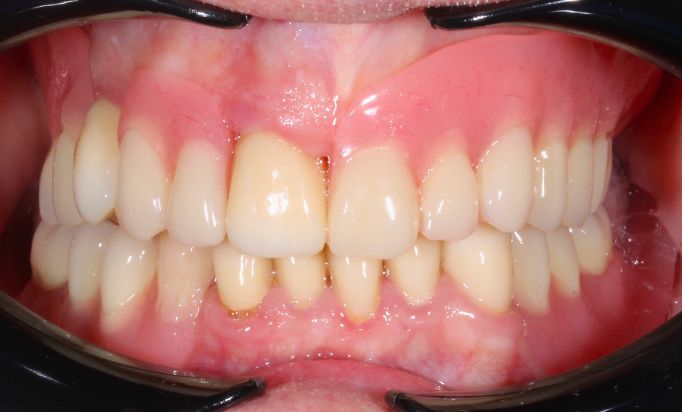

Periodontics

A secure, natural smile

Enjoy a radiant smile that reflects your personality.